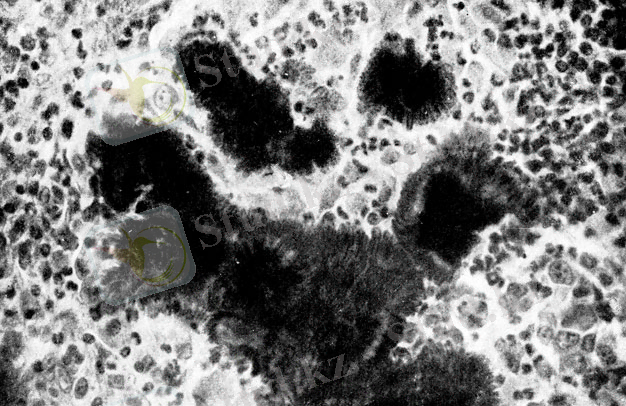

Актиномикоз (грекше aktіs (aktіnus) - сәуле және mykes - саңырауқұлақ) - актиномициттер қоздыратын жұқпалы ауру. Актимикозбен көбіне жануарлар шалдығады, ал адамдар сирек ауырады. Актиномикоз табиғатта кең тараған. Ол топырақта, жануардың ішек-қарнында, арпа-бидай дәндерінде ұзақ сақталады. Актиномикоз адам аузының шырыш қабатында, ішек-қарнында, жоғарғы тыныс алу жолында әрқашан кездеседі, бірақ зиян келтірмей тіршілік етеді. Ағзадағы қорғаныс қызметі төмендегенде (тұмау, аппендицит, туберкулез тағы басқа) адамдар актиномикоз ауруларына шалдығады. Ол көбінесе мойын терісін, асқазан мен өкпені зақымдайды. Актиномикозды операция жасау, антибиотиктер егу, сәулемен күйдіру арқылы емдейді.

Жануарлардағы патогенезі . Патогенді актиномицеттер ірі қара малдарды ауруға шалдықтырады. Кейде шошқа, жылқыларды зақымдауы мүмкін. Зақымдалу созылмалы түрде өтеді. Көбінесе тері, тіл, ерін, бет, мойын, кейде сүйек зақымдалады.

Инфекция көзі - ірі қара мал, жылқы, шошқа, ит, қоян, жабайы жануарлар және кейбір қоршаған орта объектілері (топырақ, өсімдік, ауа, дәнді дақылдар) болады. Түсу ошағы өкше болса, өкше мицетомасы дамиды. Актиномикоз асқорыту жүйесі арқылы қоздырғыштың эндогенді түсуі нәтижесінде дамиды. Дәнді дақылдарды шайнау және терінің, шырышты қабықтың зақымдалуы, әсіресе кариесті тістің болуы - аурудың ілгері дамуына әкеледі. Енген қоздырғыш дәнекер тін арқылы, қан және лимфалық жол арқылы таралады. Инфекциялық процесс инфильтраттың, іріңді аймақтардың пайда болуымен көрінеді. Ауру созылмалы қабыну, кейіннен іріңді үрдіске әкелетіндігімен сипатталады. Локализация ошағында тығыз инфильтраттар пайда болады. Тері көкшіл болады. Инфильтраттардан ұнамсыз иісті ірің шығады. Іріңде актиномицет жасушаларынан тұратын дәндер анықталады. Клиникалық көрінісі бойынша бет-мойын актиномикозын, өкпе, ішкі ағзалар, тері, бұлшықеттік, мұрын, құлақ, көмей, өңеш, ОЖЖ-нің актиномикозын ажыратады.

Возбудитель актиномикоза крупного рогатого скота - Actinomyces воvis